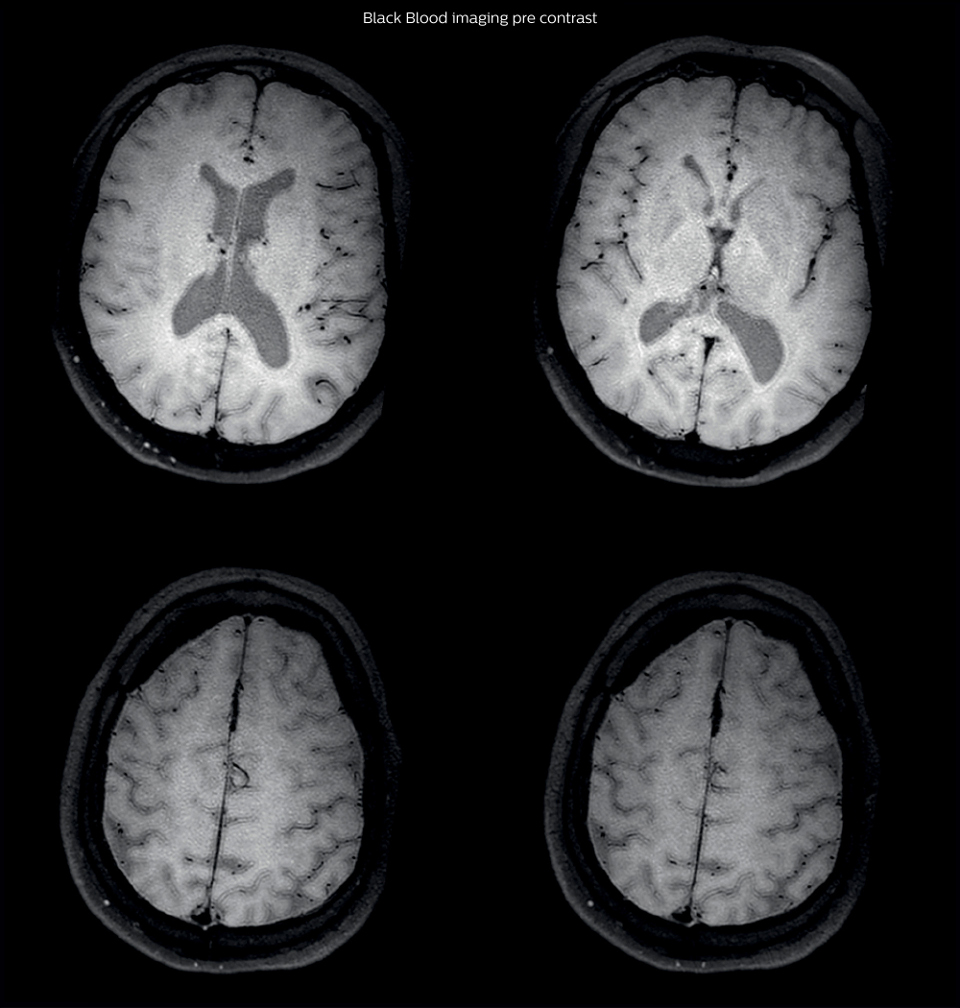

After a conventional routine MR imaging examination, the suspicion of vasculitis arose, therefore we performed an MRI including Black Blood imaging in a separate session. The dedicated ExamCard includes diffusion, FLAIR, MR angiography using TOF, and 3D T1 MRA with bolus injection. This ExamCard also includes Black Blood imaging before and after contrast. This examination was performed on our Ingenia 3.0T. Black Blood scan time 4:39 min, acquired voxel size 0.75 x 0.75 x 1.0 mm, 21 slices.

On FLAIR images we can see some nonspecific high signal abnormalities in frontal white matter bilaterally. On DWI we can see acute ischemic lesions which appear with high signal intensity. Arrows show vessel wall enhancement which appears concentric and homogeneous in different cerebral territories.

On the routine MR sequences that we did, we could see acute ischemic lesions. We see them very well on the diffusion images, where acute ischemic lesions usually appear with high signal intensity and restricted diffusion. However, the etiology of these lesions cannot be derived from these images. An area of restricted diffusion was seen in the anterior cerebral artery territory and we concluded it was an ischemic lesion. On MR angiography we can just see if there is stenosis or vessel occlusion, but it does not provide us information on the etiology of this kind of lesion. So, we decided to perform Black Blood imaging. The presence and the pattern of vessel wall enhancement on Black Blood imaging, can help us to determine the etiology of the lesion. differentiate vasculitis from other causes of vasculopathy, such as atherosclerosis, with a high specificity [1-3]. In an atherosclerotic lesion, vessel wall thickening and enhancement are usually eccentric, while in vasculitis the wall thickening and enhancement are usually concentric, homogenous, and in a long portion of the vessel. of patients whenever their treatment is installed in order to determine the efficacy of a particular treatment. In this case the Black Blood imaging helped us to suggest the diagnosis of HIV-related brain vasculitis.